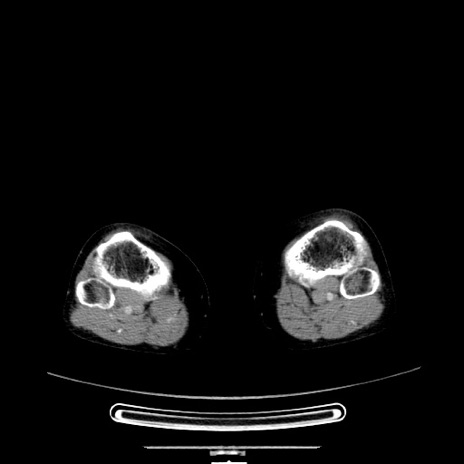

症例5(横断像)

【症例】70歳代女性

【主訴】お腹が張る

【現病歴】1週間くらい前から腹部膨満の自覚あり。昨日夜から増悪したため、本日救急外来受診。

【身体所見】意識清明、BT 36.5℃、BP 165/106mmHg、HR 80bpm、SpO2 98%、腹部:膨満、軟、自発痛・圧痛なし、触診にて不快感あり、腸蠕動音:減弱

【データ】WBC 12600、CRP 1.04